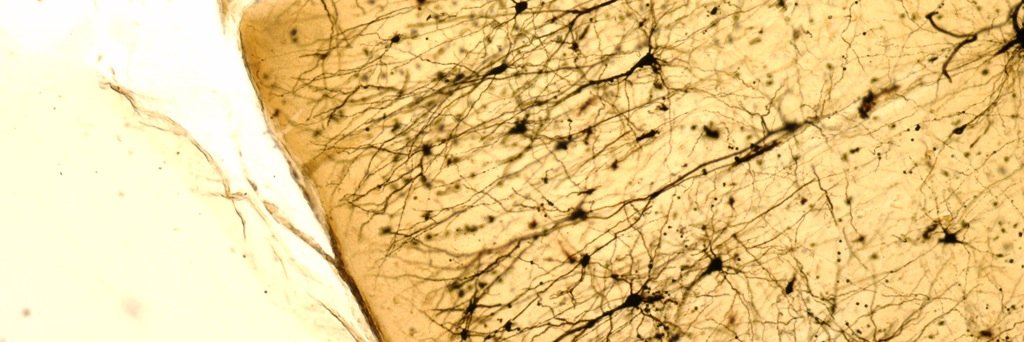

We absolutely are always looking for people with #DownSyndrome to join our research! So if you are interested or know anyone who might be interested, please do contact us at CIDDRG@medschl.cam.ac.uk and as mentioned we pay for all expenses. Help us make a real difference 🙏

Down's Syndrome Association@DSAInfo

The Cambridge Intellectual & Developmental Disabilities Research Group @CIDDRG are looking for people to take part in their research. They hope to identify early signs that may indicate Alzheimer's disease. To find out more, email ciddrg@medschl.cam.ac.uk.